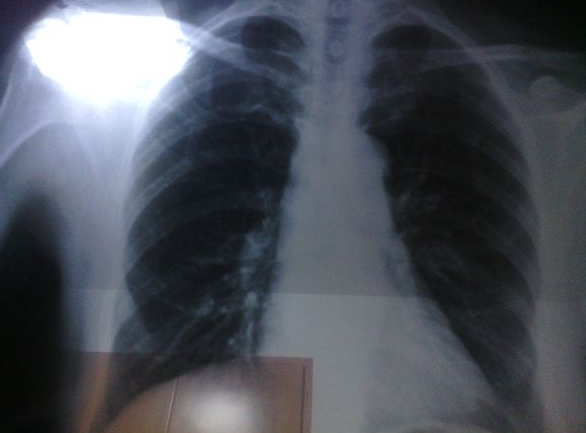

肺结节影是一种慢性发展的病症,往往首次诊断,并不能确定它的特性。到底是普通实性结节,还是恶性结节,或者只是肺部一个小炎症展现出的结节影。以8mm结节为例,随访期结节很难出现快速的扩散和转移。而且医生会根据患者身体状况、结节形态,判断随访期限,一般不会出现随访延误病情的状况。